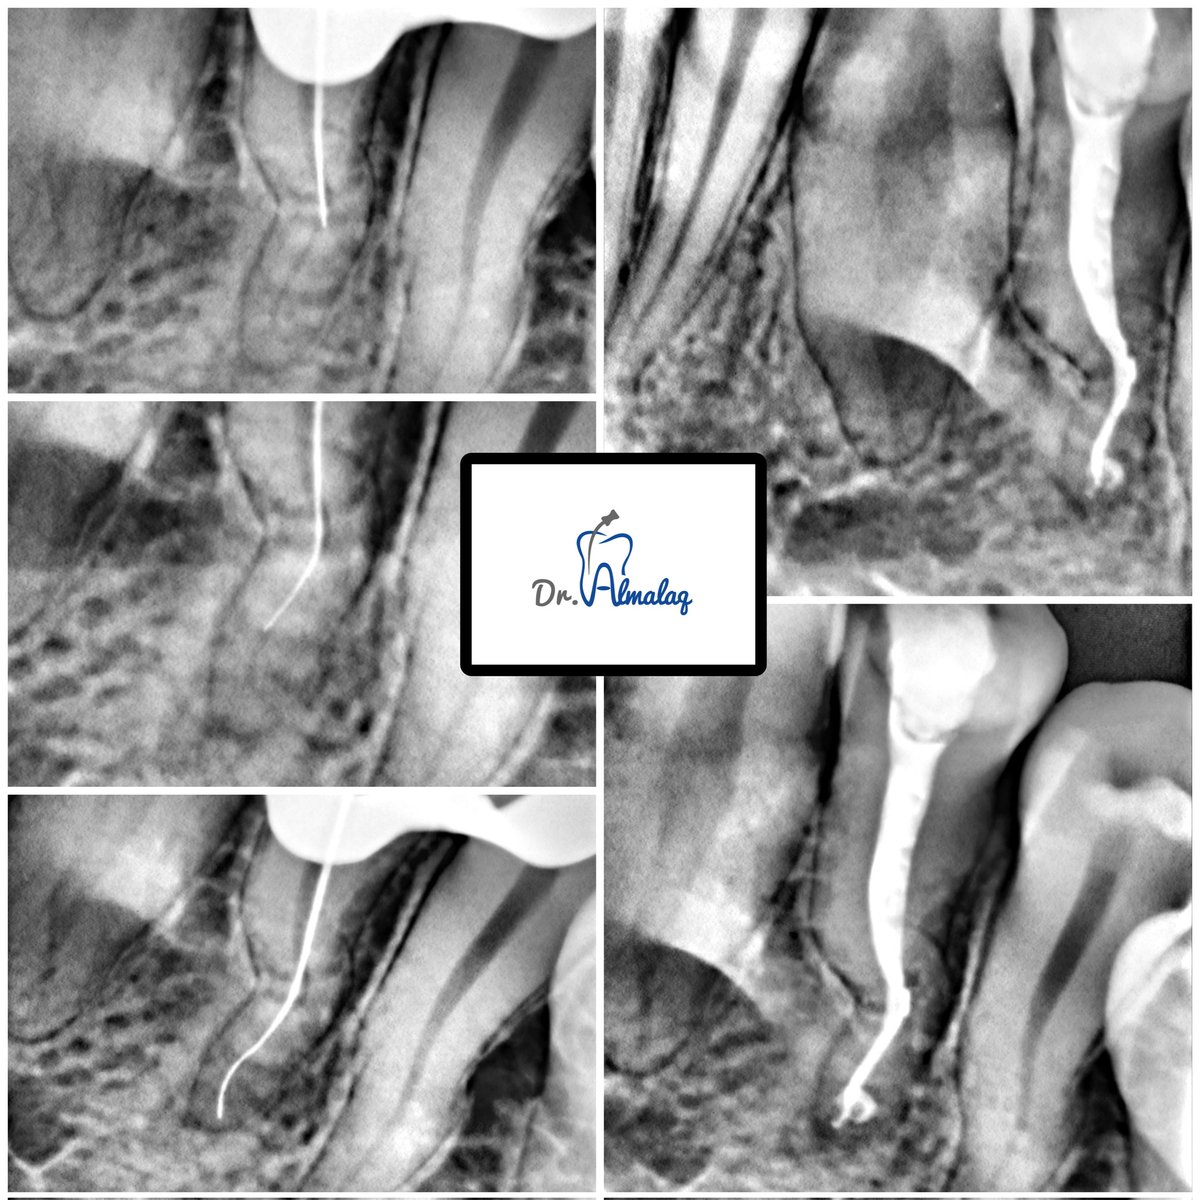

First time in my career encountering a C-shaped canal in upper first molar (#16)! Retreatment done A rare anatomy that reminds us how every case can surprise us , even the most experienced hands keep learning. #Endodontics #CshapedCanal #RootCanalTreatment #DentalAnatomy

Clinical Endodontic Case – Tooth 34 (Previously Initiated Case) Findings: ▪︎ Pre-operative radiogrph showed multiple canal curvatures with a narrow canal. ▪︎Ledge identified at the first curvature. Management: ▪︎Ledge bypassed using a short pre-curved size 10 K-file.